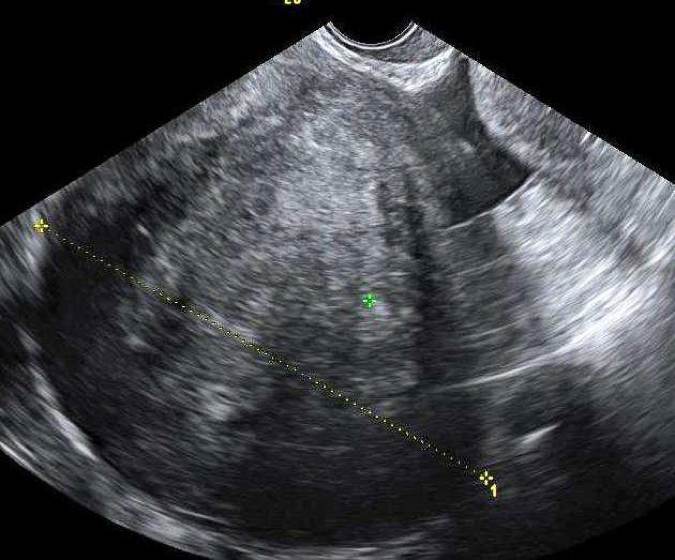

Dysgerminom är en av de vanligaste typerna av groddcellstumör och förekommer ofta hos unga kvinnor; 80 % är yngre än 30 år. Tumörformen är sällsynt hos kvinnor som genomgått menopaus. AFP- och hCG kan vara förhöjda liksom även LD. Bilaterala tumörer ses hos 10–15 % av kvinnorna. Tumörerna är solida, lobulerade, välvaskulariserade och ofta stora (10–15 cm) vid diagnos. Se bild 1.

Bild 1. Snabbväxande dysgerminom hos 22-årig gravid kvinna med förhöjt S-LD.